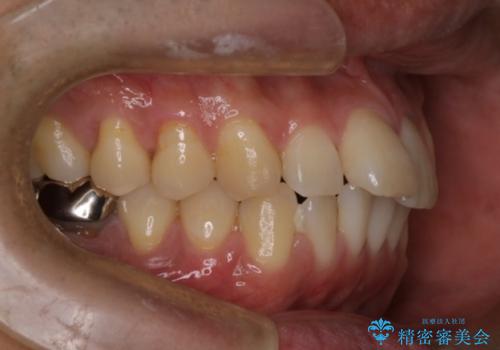

- 前歯の出ているのが気になる、下唇を噛んで痛いとのことで来院された患者様です。マウスピース矯正をご希望でした。

奥歯の噛み合わせはしっかりしていましたので、奥歯の動きは最小限にし、前歯の並びに集中した治療計画+インビザラインのシミュレーションを作成しました。

奥歯の噛み合わせは整っていたため、前歯の並びを美しく修正することに専念できました。マウスピース矯正による治療で短期間で改善しました。